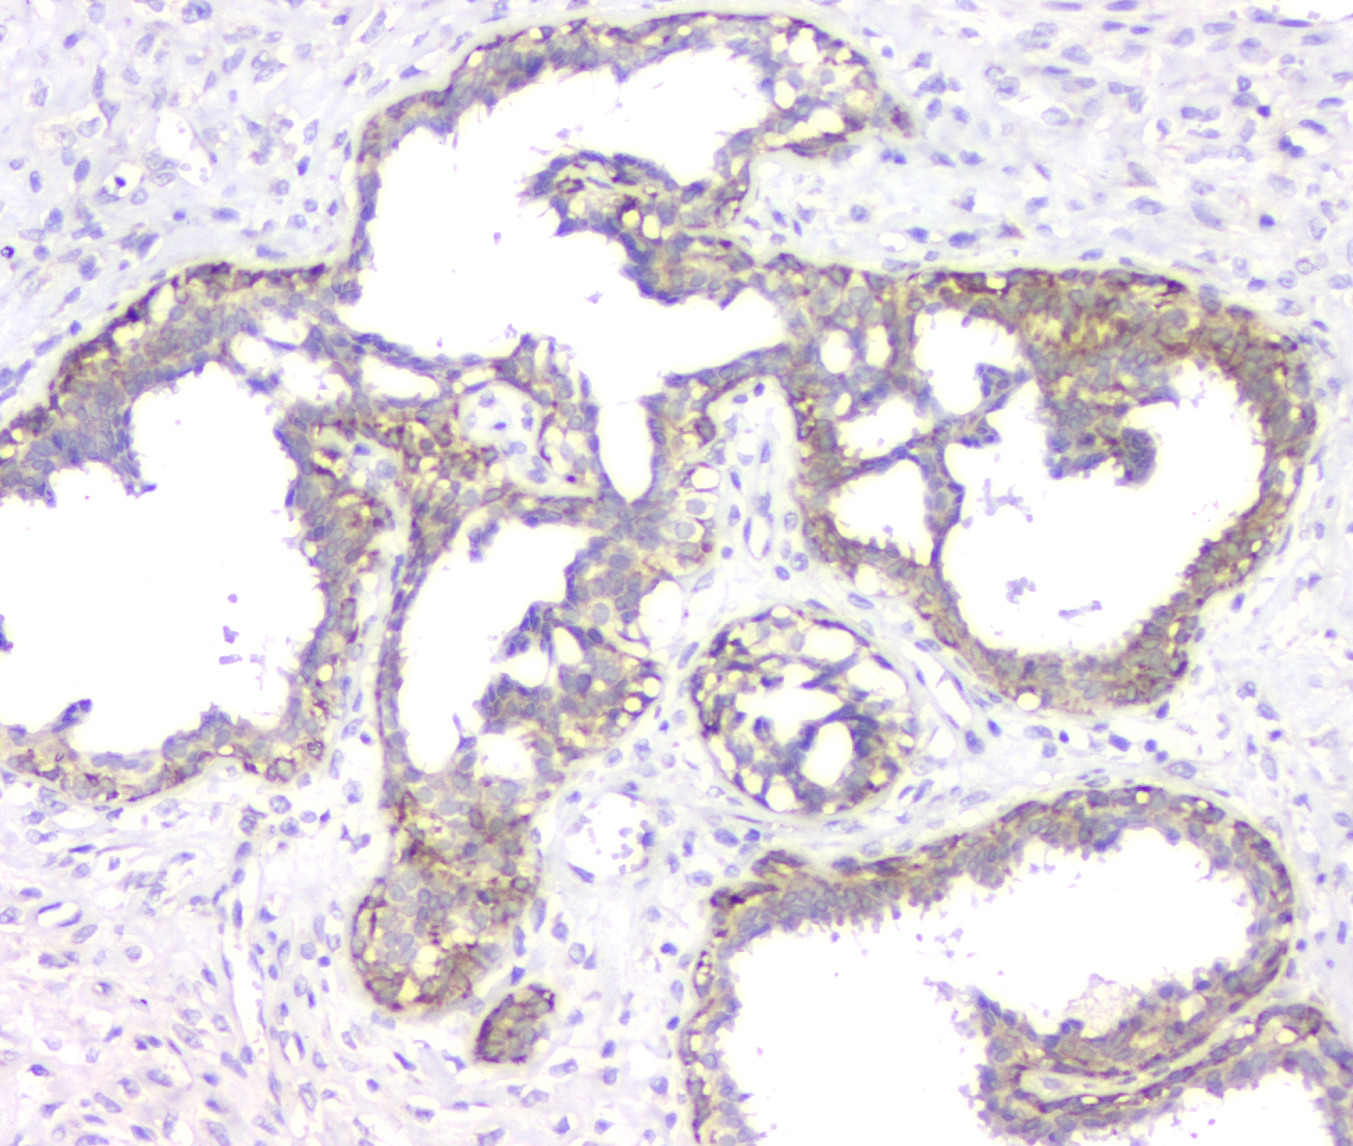

IHC analysis of RMI2 using anti-RMI2 antibody (A08685).

RMI2 was detected in a paraffin-embedded section of human mammary cancer tissue. Biotinylated goat anti-rabbit IgG was used as secondary antibody. The tissue section was incubated with rabbit anti-RMI2 Antibody (A08685) at a dilution of 1:200 and developed using Strepavidin-Biotin-Complex (SABC) (Catalog # SA1022) with DAB (Catalog # AR1027) as the chromogen.